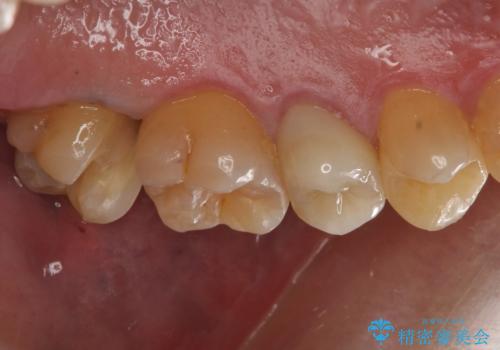

放置していた虫歯 セラミックインレーによる治療

虫歯の大きさ次第でクラウンかインレーのどちらかになるだろうとご説明させていただき、今回はセラミックインレーでの治療となりました。

- 右上7 セラミックインレー 77000円×1本費用は治療当時の料金となります

治療後は食事の際の痛みもなくなり、快適に過ごせているそうです。